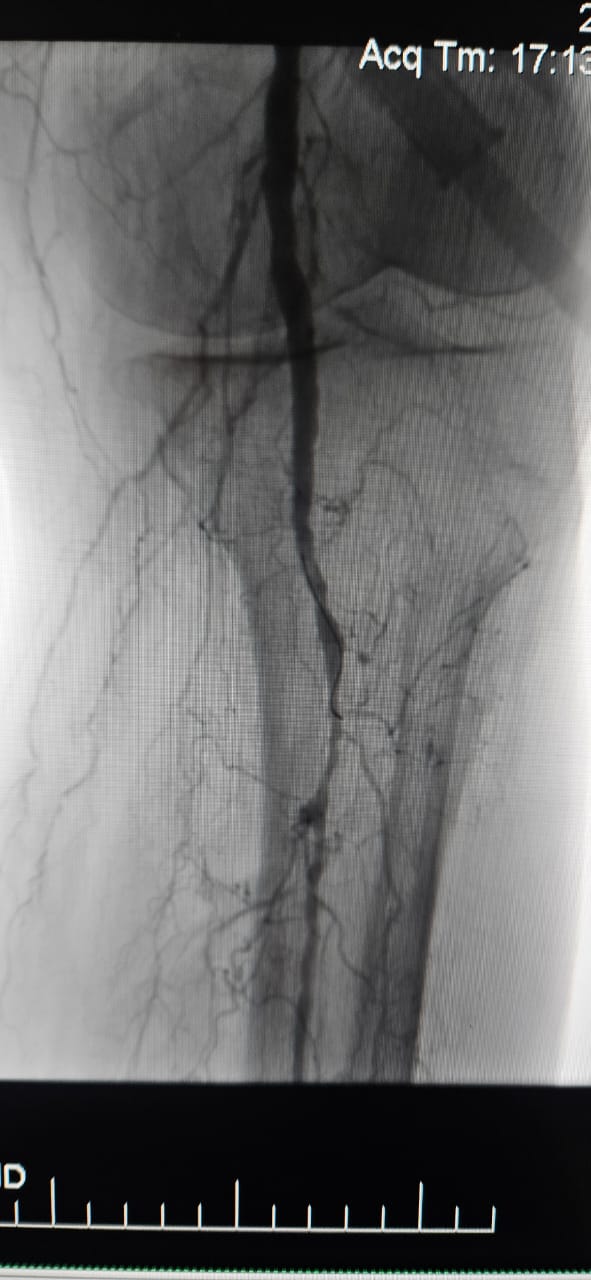

Nos complace compartir un caso exitoso de un hospital en Batumi, Georgia, donde un paciente femenino de 78 años con Isquemia Crítica de Extremidades (CLI) causada por oclusión total crónica de la arteria del miembro inferior mostró una mejoría clínica notable después del tratamiento con el sistema periférico de catéter de dilatación con balón IVL de ThorCrack.

Este caso subraya el valor clínico de la litrotripsia intravascular (IVL) en el tratamiento de casos complejos de CLI con oclusión crónica de segmento largo, particularmente en pacientes con calcificación pesada, donde los balones tradicionales o los dispositivos de aterectomía pueden tener una eficacia limitada.

Estamos orgullosos de ver a ThorCrack IVL capacitar a los médicos de todo el mundo para superar lesiones calcificadas, restaurar la perfusión y mejorar los resultados de los pacientes en la enfermedad arterial periférica compleja.